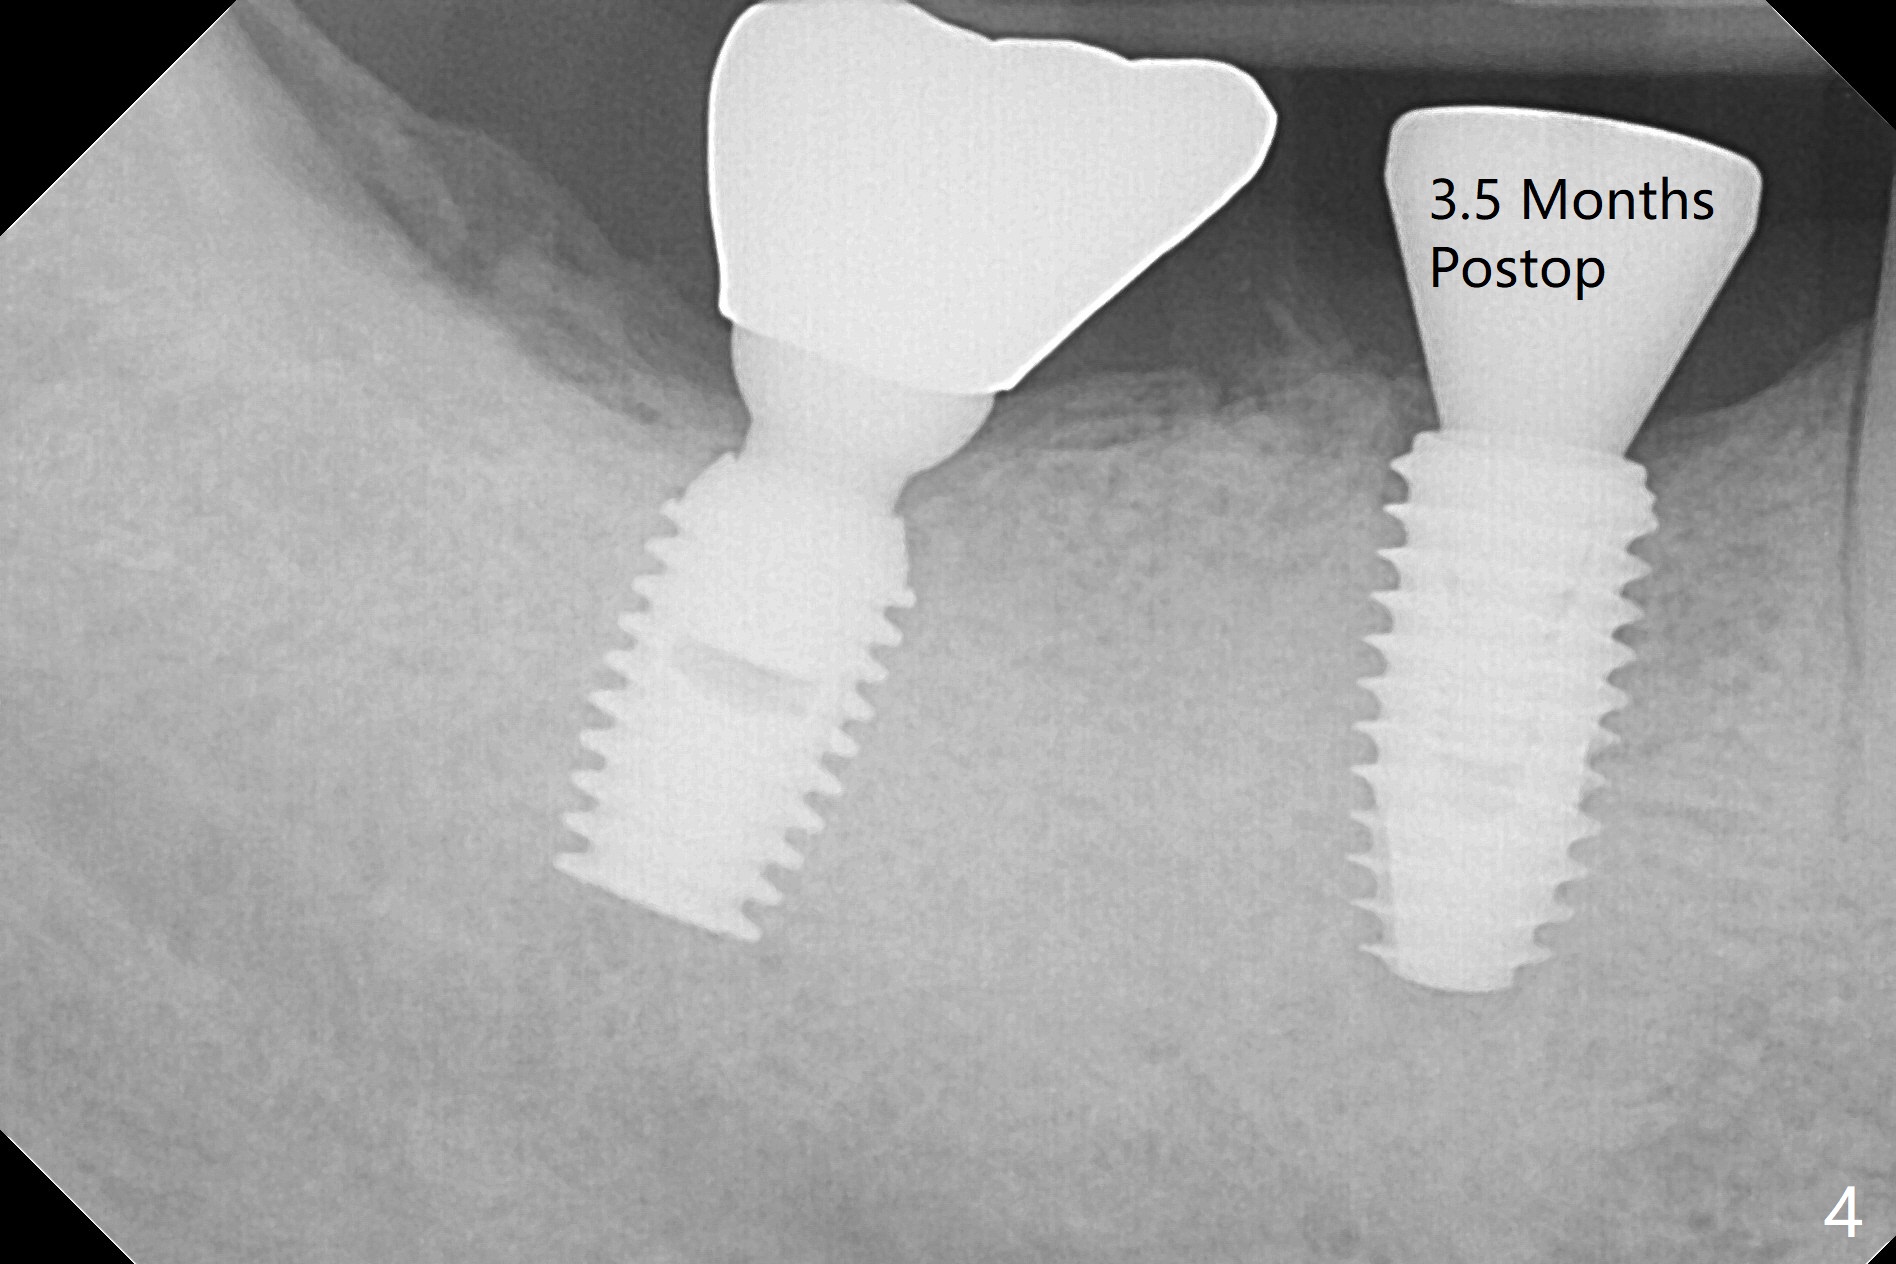

Vertical fracture of the mesial root of the tooth #30 after RCT is associated with bone loss (Fig.00 *). When the mesial portion of the mesial root (M', loose one) is exfoliated, the bone loss resolves (Fig.0). To reduce heat-induced bone necrosis at #19, osteotomy is conducted slowly with copious irrigation with cold saline. Bone density is felt while a 5x10 mm implant is being placed after using cortical tap to the 2nd line of the implant driver. The implant needs to be reverse torqued several times before reaching its final depth (Fig.1 (~50 Ncm)). Since the residual roots are superficially positioned, the immediate implant looks as a delayed one. Although the implant is placed mesial to the septum clinically, its position in X-ray seems to be normal. Because of severe wear and lack of vertical height, a 6.8x5 mm healing abutment is placed. Retention of bone graft (Fig.1 *) is maintained by spreading setting acrylic into the edentulous undercut areas (Fig.2 *). The so called "acrylic dressing" remains in place 3 weeks postop (Fig.8). When it is removed with the healing abutment, the wound heals (Fig.3). Note the limited vertical height. The bone graft placed in the distal socket appears to have been converted to the native bone 3.5 months postop (Fig.4). To reduce severe wear of the natural teeth, the occlusion of the new crown is not heavily decreased (Fig.5). It should be alright considering favorable crown/implant ratio (Fig.6). There is no bone loss 5 months post cementation, although the abutment screw is just retightened (Fig.7). In spite of poor trajectory associated with #18 (Fig.8) and 31 (Fig.7) Bicon implants, the abutments have not been dislodged. For the bruxer, the next implant at #19 with distal root fracture (Fig.8 ^) should be Bicon. The patient complains of food impaction nearly 1 year post cementation. The mesial and distal contacts of #30 crowns are light. When the abutment/crown is removed, there is implant well contamination (food debris). It appears that the previous abutment (5.7x4(2) mm, Fig.6,7) is incompletely seated. When a smaller abutment is placed and torqued at 30 Ncm, it is seated fully (Fig.9 (<: no gap)). New impression is taken. The distal gingival embrasure is larger than the mesial one because of the higher distal crest (Fig.6,7). If there is food impaction distal to the new crown, the distal crestal bone should be removed with lab closure of the embrasure.